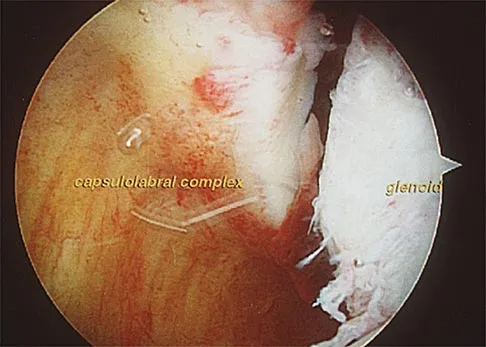

An 18-year-old hockey player sustains an acute anterior shoulder dislocation that requires manual reduction. At arthroscopy, the lesion shown in Figure 24 will be observed in what percent of patients?